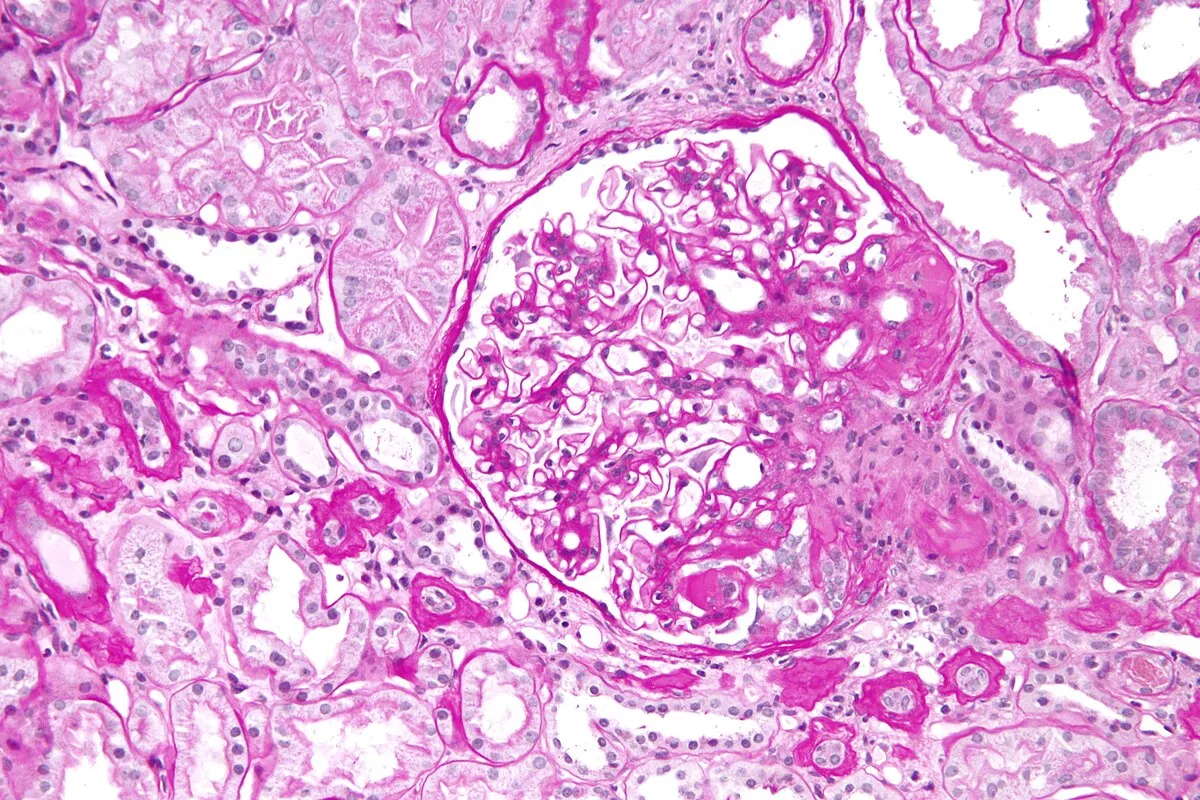

Este vídeo apresenta, de forma didática e baseada em evidências, os principais achados da tese de doutorado sobre amiloidose renal, com foco em proteômica glomerular e ativação do complemento. São discutidos aspectos diagnósticos, implicações fisiopatológicas e correlações clínico-patológicas relevantes para a prática do nefrologista. O conteúdo sintetiza dados inéditos de matriz extracelular glomerular e diferencia perfis entre subtipos de amiloidose. Trata-se de um material aprofundado e acessível, ideal para atualização de especialistas na área.